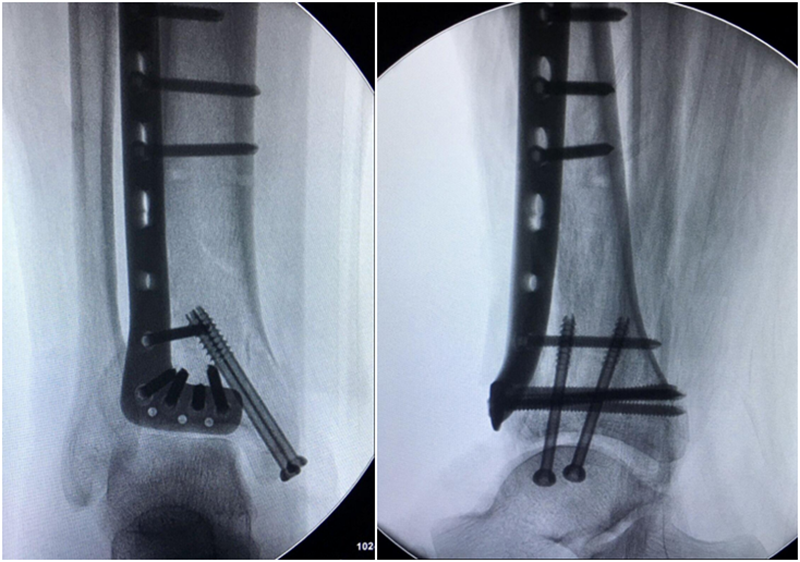

术中资料:切口与术中C-臂检测

图9 手术L切口远端横臂切口略偏近端,踝关节显露稍显不足,经延长“L”切口横臂后解决

图10 术中

术后影像学资料: